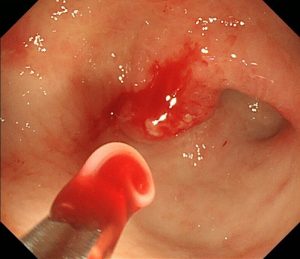

2匹目です。胃体上部(胃の入り口付近)に食いついています。

同様に鉗子で除去します。